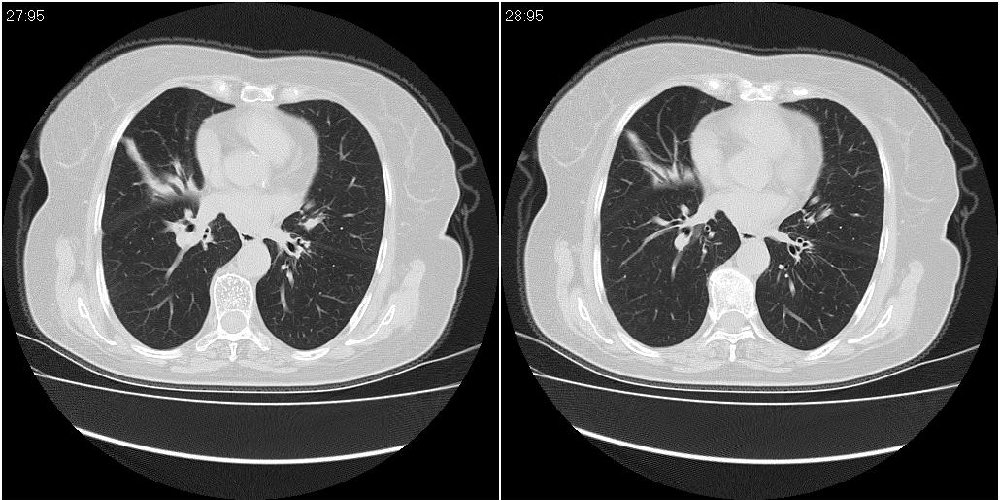

女性,72岁。去年9月份发现肺部病变,诊为肺结核并进行正规治疗至今,但复查后发现ct表现几乎没有变化。

右中间段支气管局限性狭窄,右中叶支气管亦稍显狭窄,但并未见明显占位表现,半年多了,无变化也许是好事,可能为炎性狭窄,建议继续随访。

双肺继发型tb并右中叶内膜tb,轻度支扩,左下胸膜肥厚粘连。

右中间段支气管局限性狭窄,右中叶支气管亦稍显狭窄.

双肺继发性肺结核并右肺中叶节段性肺不张,左下胸膜肥厚粘连。

右肺中叶节段性肺不张,考虑结核或慢性炎症,建议做纤支镜检查。

双肺继发性肺结核并右肺中叶节段性肺不张